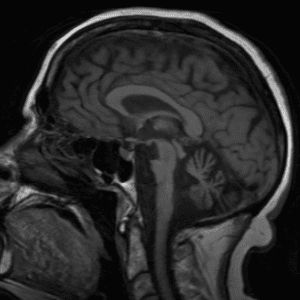

Neurodegenerative Diseases